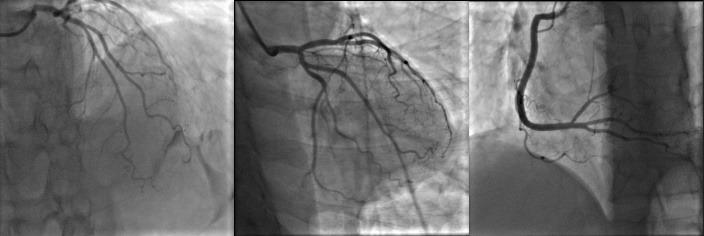

Spontaneous coronary artery vasospasm is one of the important causes of acute chest pain syndromes. The diagnosis of diffuse multifocal spasm can be quite challenging and it could be easily mistaken for diffuse coronary artery disease. The use of intracoronary nitroglycerin can relieve spasm and reveal the real extent of coronary artery disease. Herein we present a case presenting with acute myocardial infarction due to severe coronary artery spasm that had even received fibrinolytic therapy. Multiple narrowing was shown during coronary angiography and the patient was scheduled for percutaneous coronary intervention (PCI). But after intracoronary (IC) injection of nitroglycerin, all of lesions disappeared completely and the diagnosis of coronary spasm was confirmed.

自发性冠状动脉血管痉挛是急性胸痛综合征的重要病因之一。弥漫性多灶性痉挛的诊断颇具挑战性,很容易被误诊为弥漫性冠状动脉疾病。冠状动脉内使用硝酸甘油可缓解痉挛并揭示冠状动脉疾病的实际范围。在此,我们报告一例因严重冠状动脉痉挛导致急性心肌梗死的病例,该患者甚至接受了溶栓治疗。冠状动脉造影显示多处狭窄,患者计划接受经皮冠状动脉介入治疗(PCI)。但在冠状动脉内(IC)注射硝酸甘油后,所有病变完全消失,冠状动脉痉挛的诊断得以证实。